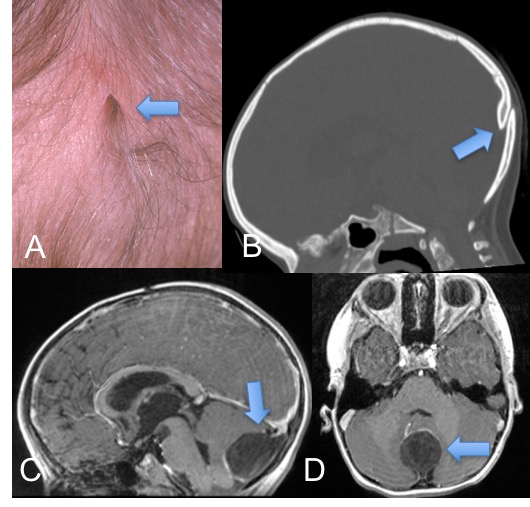

- une anomalie cutanée, vue à la naissance alors que les cheveux sont fins et transparents (A): c’est une fossette centrée par des cheveux plus épais et sombres

- parfois, elles se présentent comme une masse intracrânienne (C, D) par accumulation de squames d’épiderme (kyste dermoïde)

l’imagerie montre un pertuis osseux (B), rarement une masse intracrânienne (C, D)